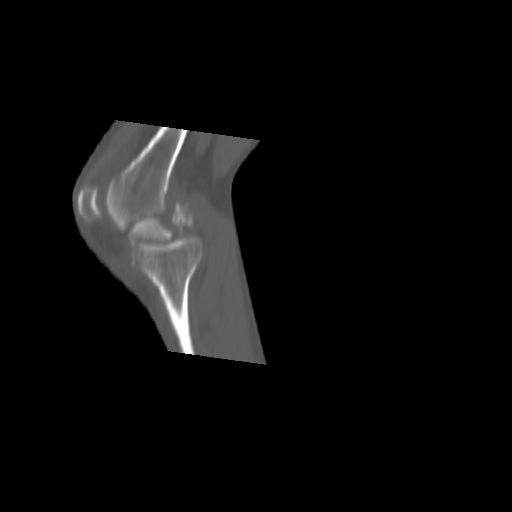

Before the CT and MRI era, we were treating the fractures with study of the Xrays alone. Such fractures with skeletal traction followed by non wtbearing mobilisation used to yield a fairly good range of movements. The CT gives a real ghastly picture of not so bad looking plain Xrays. I think this case needs traction to start with to correct the flexion deformity which probably will be achieved in 2 weeks time or less. We can then reassess the case with fresh Xrays. If possible one should try and fix the fragments to get some alignment. But the fixation should be stable enough to be able to mobilise the joint. Otherwise the traction can be continued for another 2 weeks to make the fracture sticky and then mobilise. We could get about 70 to 80* movements in spite of such communition. I am enclosing an Xray of a patient who is walking independantly and has 0 to 80* movemnts of the knee for the last one year